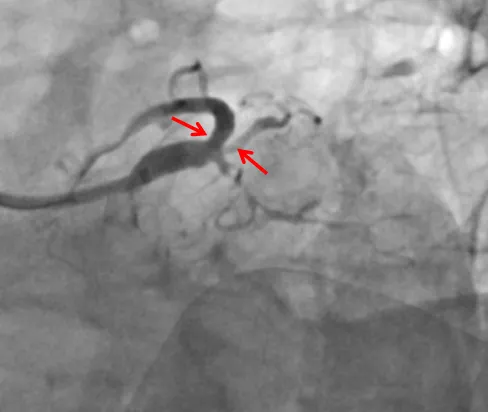

▲右冠脉多发弥漫严重狭窄,缺血风险高

▲植入支架后,冠脉狭窄较前明显减轻